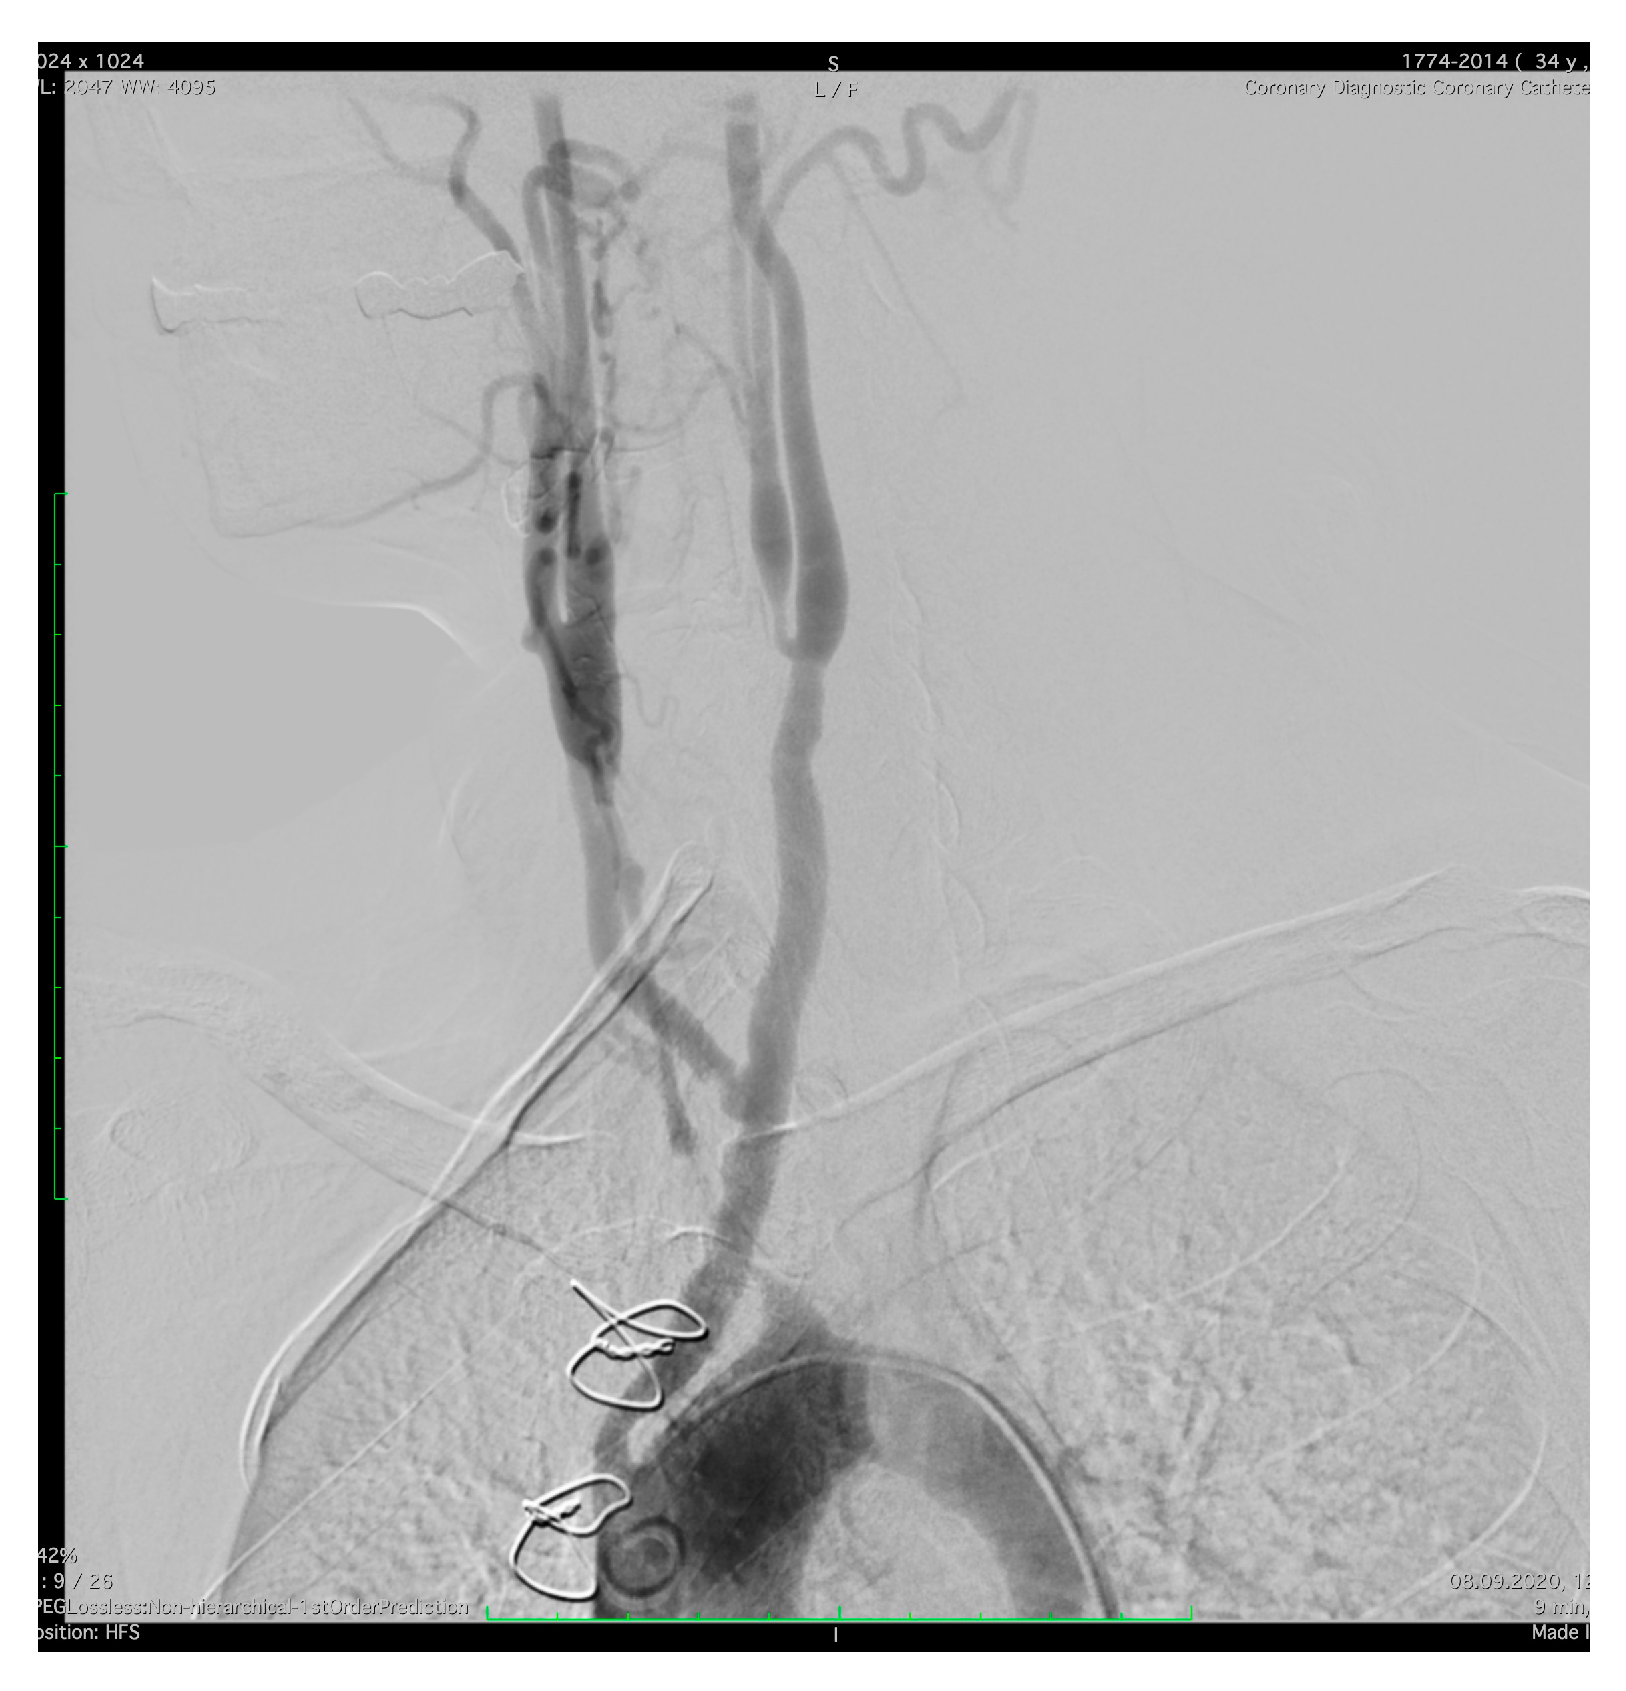

Figure 4.

Aortography of the ascending aorta and aortic arch. Anteroposterior projection: occlusion of the right and left subclavian artery, occlusion of the left common artery, patent-bi-carotid bypass with 50% stenosis of the right branch proximal.